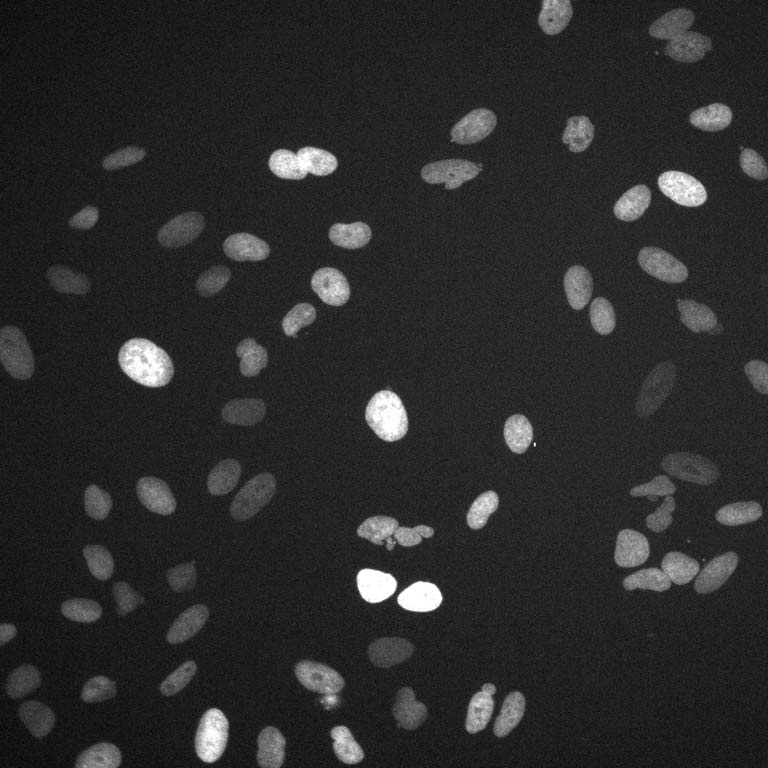

This picture shows cancer cells after being treated with a chemotherapy drug. Using these images, I am able to link how these cells are processing outside information during chemo treatment with what type of cancer cell they will eventually turn into days later.

My project focuses on how MAPK pathways help cells choose between senescence and proliferation after DNA damage. I took time-lapse live-cell images with cells expressing fluorescent reporters for the Jnk (magenta channel) and Erk (green channel) kinase pathways. When either of these pathways is turned on, you can see the fluorescence localization change from the nucleus to the cytoplasm. After treating an osteosarcoma cell line (U2OS) with a low-dose of doxorubicin for 4 hours, I wanted to see how very early Jnk and Erk dynamics differentiated cells that became senescent with cells that continued to proliferate days under different inhibitor conditions.